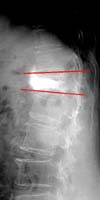

<ôÃ߾йڰñÀý½Ã

dz¼±Ã´Ãß¼ºÇü¼ú½ÃÇà·Ê>

<¼ö¼ú

Àü> <¼ö¼ú½ÃÇà·Ê>

ÈÄ>

°ñ´Ù°øÁõȯÀÚ¿¡¼

ôÃ߿ܻóÀ¸·Î ÀÎÇÑ Èä¿äÃߺΠ¾Ð¹Ú°ñÀý¿¡¼

dz¼±¼ºÇü¼ú ½ÃÇà¸ð½À

<ôÃߺмâ°ñÀý½Ã

Ã߰泪»ç¸ø°íÁ¤¼ú ½ÃÇà·Ê>

Àü> <¼ö¼ú

ôÃ߿ܻóÀ¸·Î

ÈäÃߺΠºÐ¼â°ñÀýȯÀÚ¿¡¼ Ã߰泪»ç¸ø °íÁ¤¼ú

½ÃÇà¸ð½À |